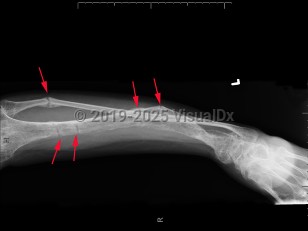

Clinical presentation is variable and typically presents after 18 months of age or when the pediatric patient begins to walk. Symptoms range from growth retardation and short stature to severe rickets or osteomalacia. Some patients have isolated hypophosphatemia detected on serologic testing. The typical presentation is a child with leg bowing and other bone deformities, pseudo-fractures, bone pain, and short stature. Rarely, a patient may present with tetany, dental enamel defects, and spine or pelvic rickets.